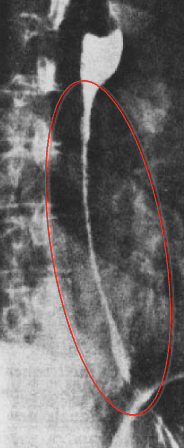

<p>What esophageal disorder is this?</p>

What esophageal disorder is this?

Malignant stricture